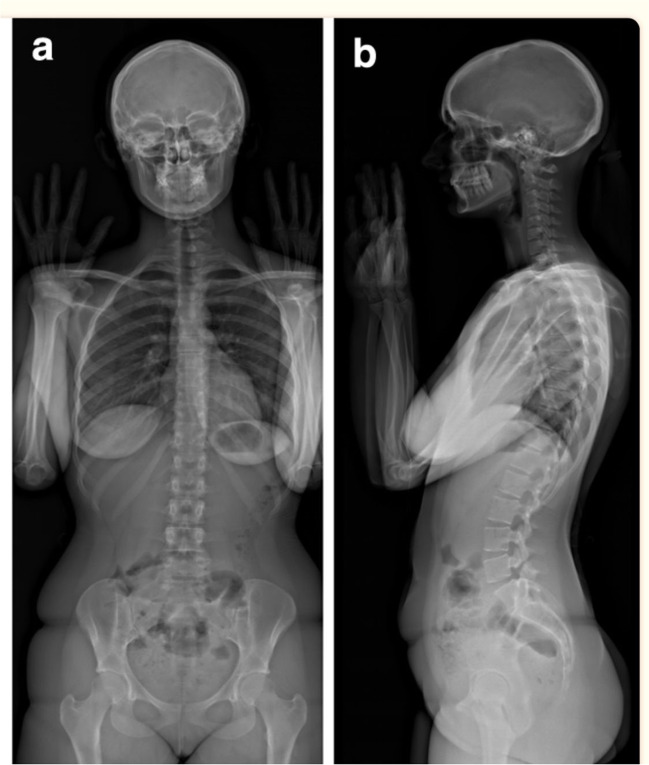

A new X-ray imaging device has been developed which incorporates this novel detection technology. It consists of two co-located pairs of 45-cm wide linear radiation sources and detectors that are perpendicular to one another and positioned both frontally and laterally [25, 26] (Fig. 2) [27]. Biplanar X-ray images are captured simultaneously within this X-ray imaging device, dubbed EOS 2D/3D, via the vertical movement of two pairs of X-ray tubes and detectors. This vertical movement covers a 170 cm high × 45 cm wide area, producing high-quality, high-contrast anteroposterior (AP) and lateral (LAT) X-ray images in as little as 10–25 s [25, 26] (Fig. 3) [28]. Additionally, rigorous 3D reconstructions of the pelvis, vertebrae and other skeletal sites can be produced (Fig. 4) [29].

Fig. 3.

Full body on simultaneously captured images of anteroposterior (AP) (left) and lateral (LAT) (right) [28]